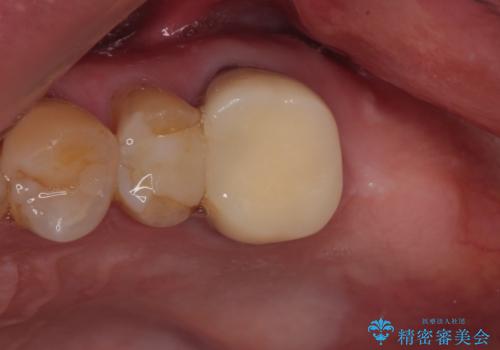

- 破損したクラウンと、奥歯の欠損を気にして来院された患者様です。

奥歯の欠損部はインプラントによる補綴治療を、手前の破損したクラウンは作り替えをご希望でした。

口があまり開かず、インプラントの埋入角度がやや斜めとなりましたが、機能的には全く問題なく治療を終えることができました。